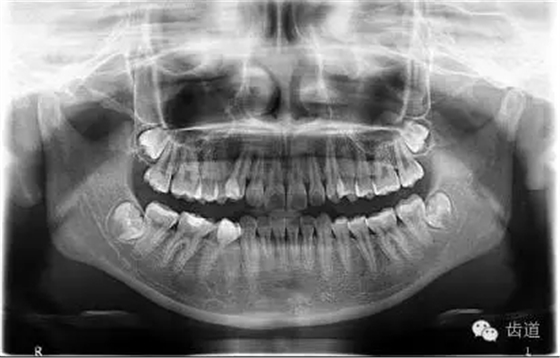

1.術(shù)前全景片

可見(jiàn)37根尖周有明顯透射影像(患者當(dāng)日懷疑第三磨牙阻生問(wèn)題,初診科室為外科,擬行雙側(cè)阻生齒拔除術(shù),故已向行全景片拍攝)